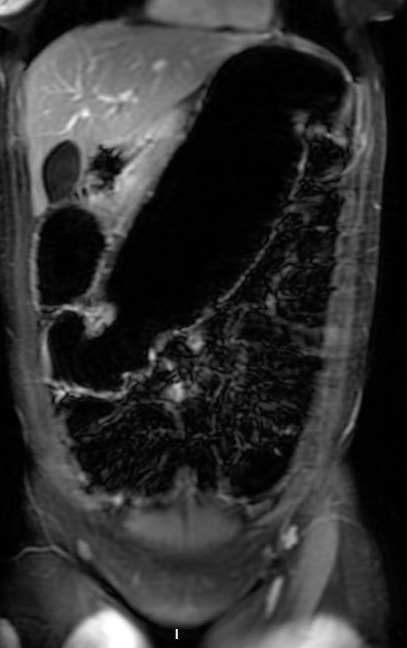

Magnetic resonance enterography on hospital day 7 confirmed mural thickening and luminal narrowing of the descending colon with upstream distension, findings suggestive of a chronic stricture (Figure 1C). Moderate-volume pelvic ascites was also present, although there were no imaging features of portal hypertension. An extensive infectious and inflammatory evaluation, including stool cultures, ova and parasite examination, celiac serologies, tuberculosis testing, and serologic testing for Entamoeba histolytica, was unrevealing. Although ascites was present, no safe fluid pocket was available for diagnostic paracentesis. Because of progressive obstructive symptoms, worsening colonic dilation, and persistent diagnostic uncertainty despite extensive noninvasive evaluation, laparoscopic-assisted subtotal colectomy was performed on hospital day 8. Empiric immunosuppressive therapy for Crohn’s disease was deferred throughout the evaluation because of the absence of classic endoscopic features of inflammatory bowel disease and concern for an alternative diagnosis. Intraoperatively, multiple colonic strictures, adhesions involving the pancreas and spleen, mesenteric lymphadenopathy, and diffuse gastric wall thickening were identified.